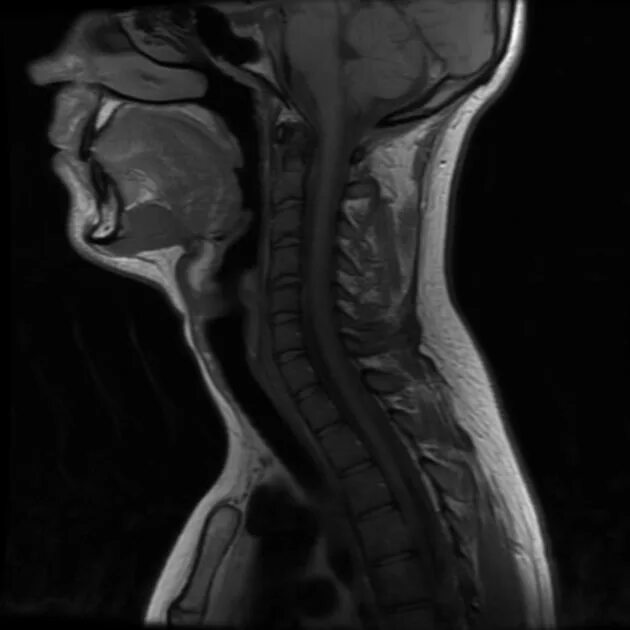

Сколько по времени делается мрт шейного отдела